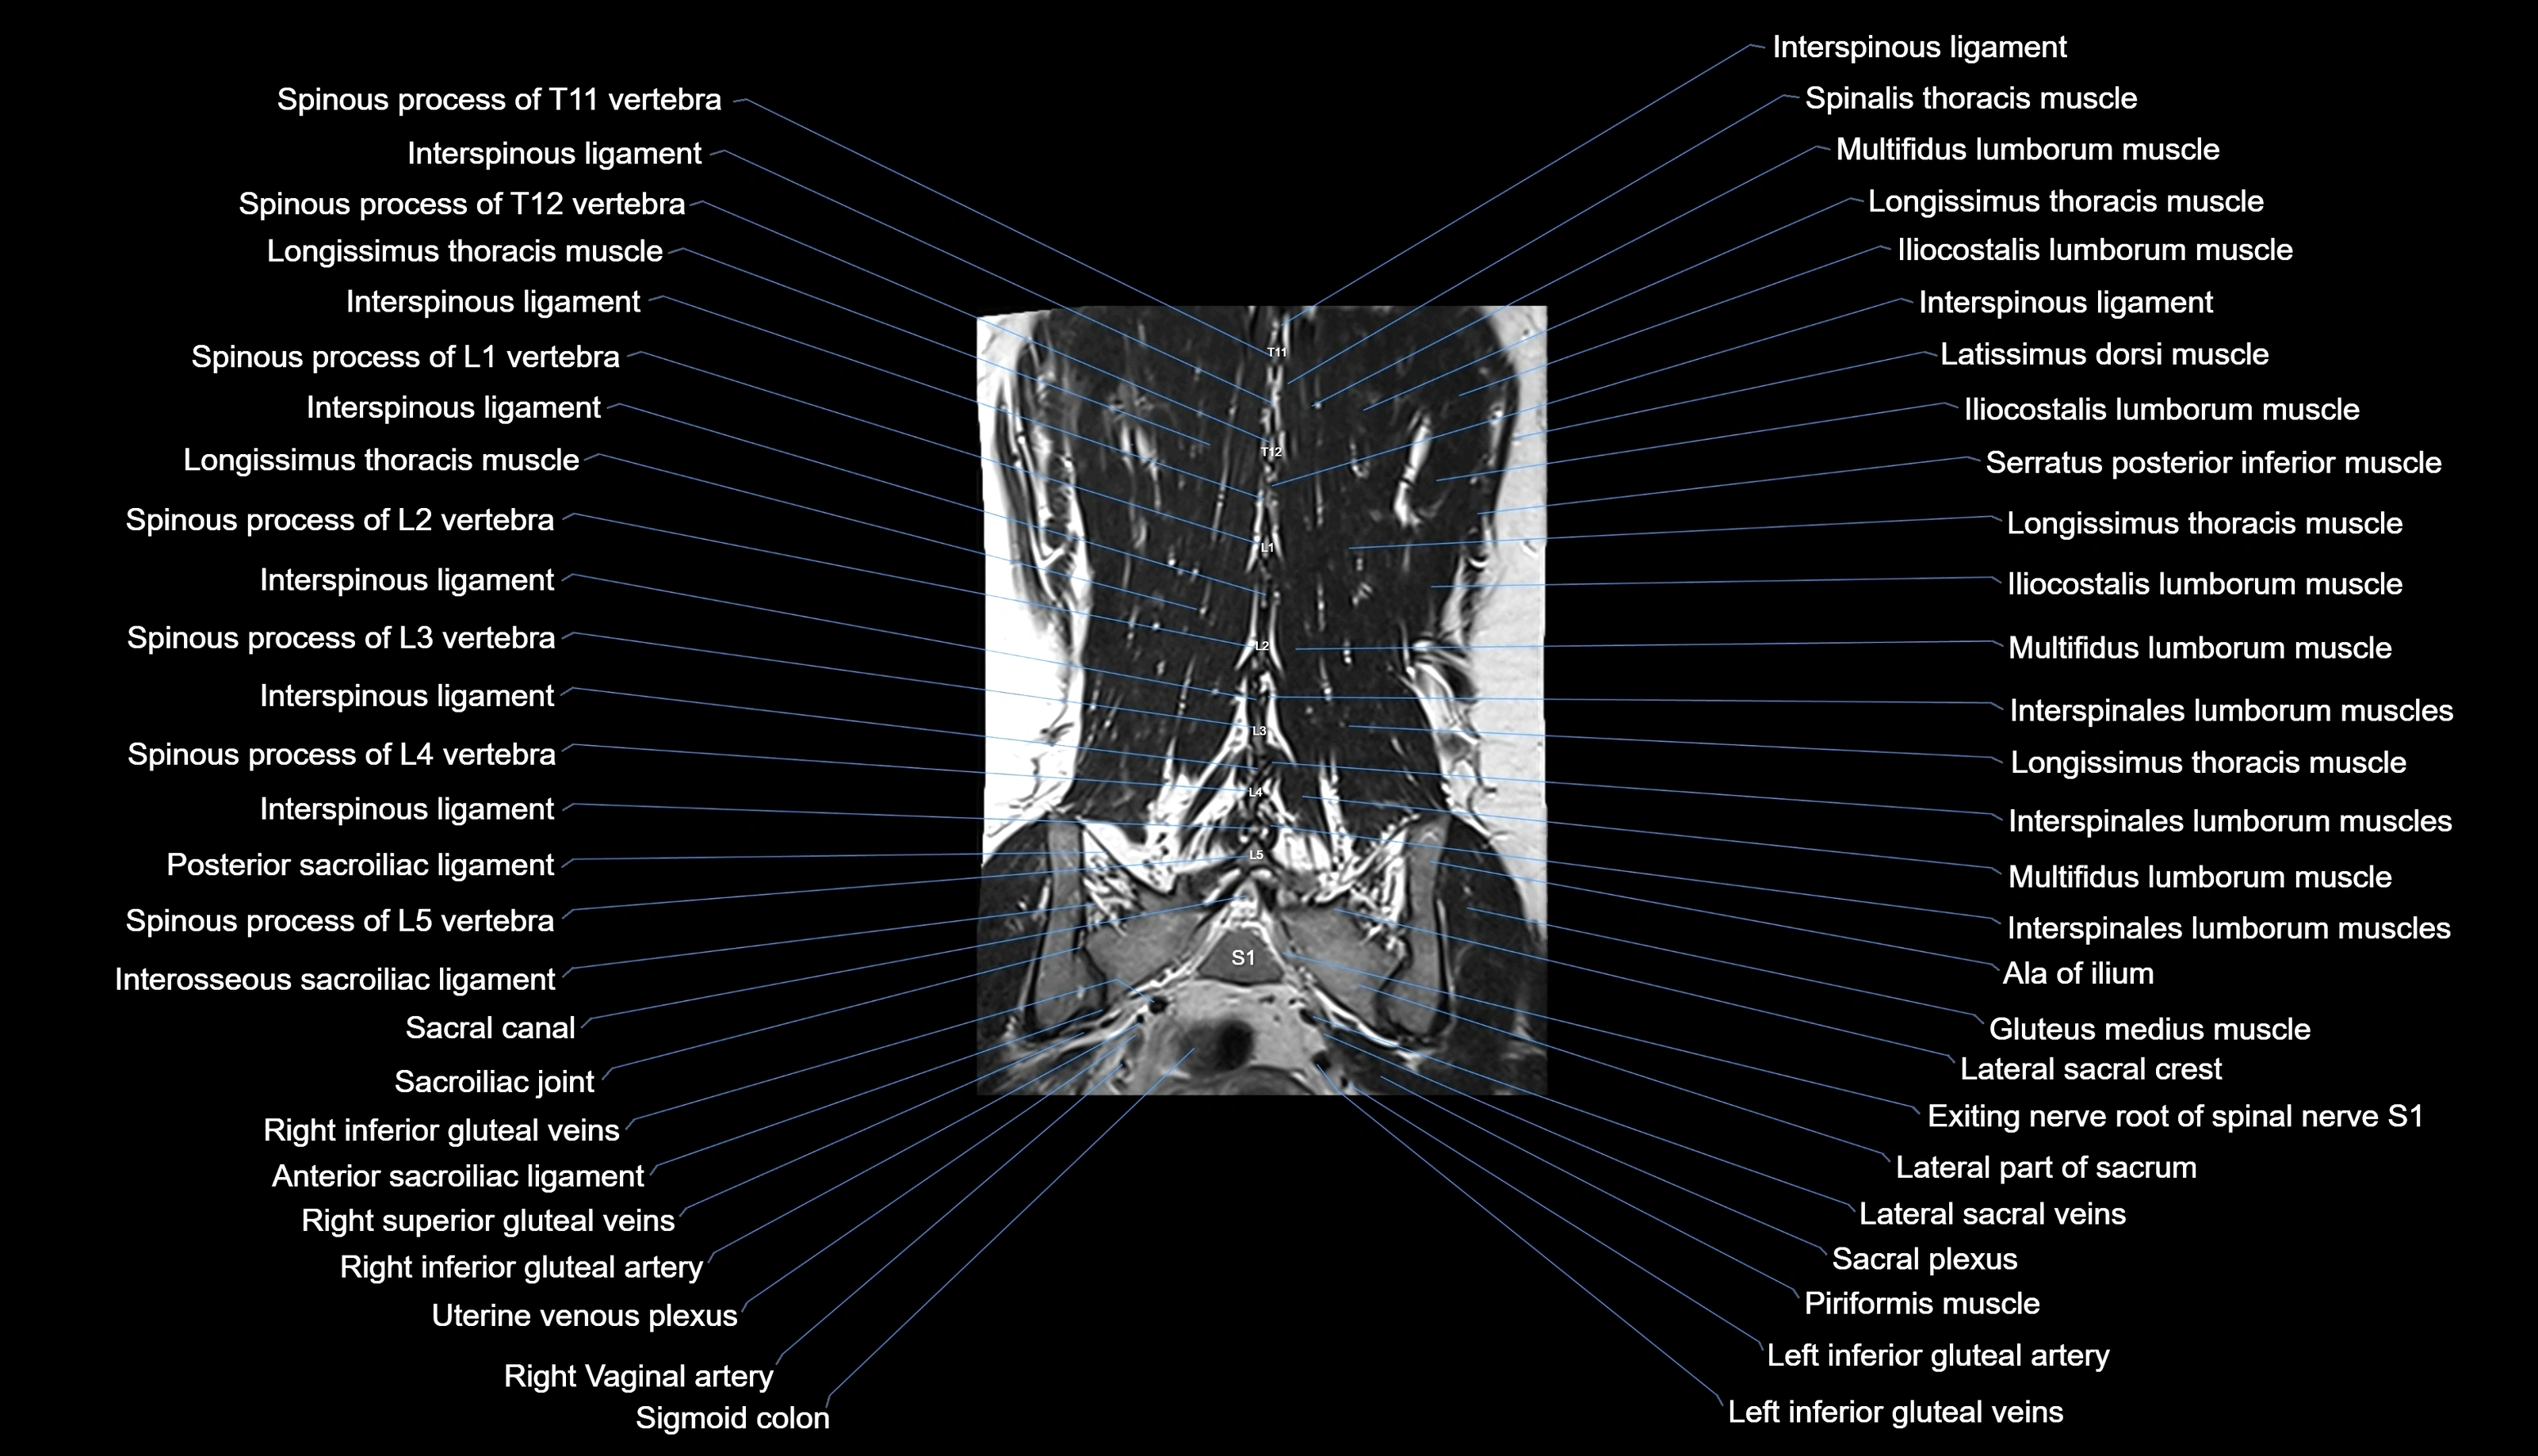

MRI images